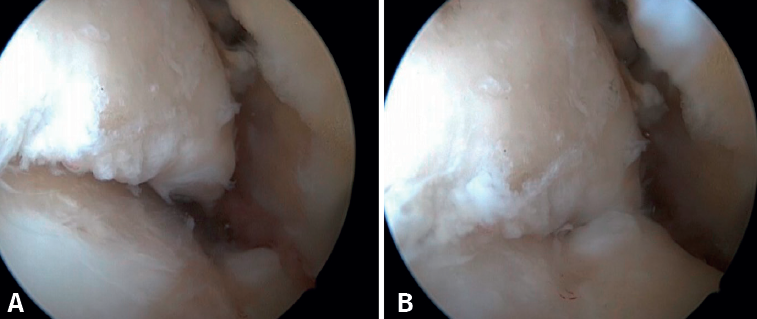

El PAT óseo por osteofitos también ha sido relacionado con la presencia de inestabilidad crónica. Se ha postulado que la alteración en la cinemática articular secundaria a la insuficiencia ligamentosa favorece el desarrollo de osteofitos en la región anterior de la tibia y el astrágalo(36,37). Estudios recientes han cuestionado la teoría de tracción capsular repetida como origen de los osteofitos en la práctica deportiva(38), ya que es fácilmente demostrable que los osteofitos se localizan intraarticulares por dentro de la inserción capsular, en el contexto de una artroscopia de tobillo (Figura 2). Por ello, la artroscopia con dorsiflexión de tobillo es fundamental para poder resecar los osteofitos de forma segura sin daño capsular ni a las estructuras suprayacentes, mientras que la técnica clásica de tracción (invasiva o no) dificultaría enormemente su resección, por lo que hoy en día se desaconseja su uso rutinario(3,39). Vega distingue dos tipos de osteofitos(3), según sean por trauma repetitivo (forma de pico) o por inestabilidad (en forma de visera). El concepto de microinestabilidad se asocia a microtraumatismos de repetición que podrían ser el origen de osteofitos con esta morfología característica (Figura 3).

El ligamento de Bassett debe conservarse siempre que no tenga un aspecto patológico, descartando engrosamientos, roturas parciales o lesiones recíprocas en la superficie anterolateral del astrágalo (Figura 6), que se asocian a inestabilidades anterolaterales o rotatorias. La inserción peroneal se usa como referencia para localizar la inserción distal del LTFA. Debe inspeccionarse el ligamento deltoideo en la gotera medial en caso de sospecha de inestabilidad rotatoria asociada. Durante la artroscopia, se puede realizar una reparación directa de los ligamentos mediante suturas y anclajes.

Figura 3. Osteofito por inestabilidad crónica. A: el osteofito conforma un tope óseo que se extiende en el borde anterior del plafón tibial y la cara anterior del maléolo medial; B: imagen artroscópica.

Figura 6. Surco producido por el roce de la cúpula talar con el ligamento de Bassett, visible tras la resección de este. El ligamento presentaba una rotura parcial y un engrosamiento cicatricial.